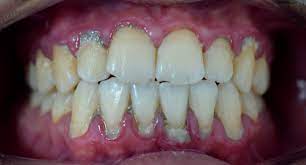

치주염 증상

치주염(Periodontitis)은 입안 건강에 영향을 미치는 질환으로, 다양한 증상을 보일 수 있습니다. 아래에 치주염의 주요 증상을 자세히 설명해 드리겠습니다:

1. 잇몸 출혈: 가장 흔한 치주염 초기 증상 중 하나는 잇몸 출혈입니다. 칫솔질, 치실 사용, 또는 딱딱한 음식을 먹을 때 잇몸이 출혈할 수 있습니다. 잇몸 출혈은 염증으로 인해 잇몸 조직이 약화되고 혈관이 더 가시적으로 되기 때문에 발생합니다.

2. 치아 주위 붓기: 치주염이 진행되면 잇몸 주위 조직이 붓게 됩니다. 이로 인해 잇몸이 붓고 부풀어오르며 거의 항상 충혈된 상태를 유지합니다.

치주염의 증상은 조직의 염증과 치아 주변 조직의 파괴로 인해 발생하며, 증상의 심각성은 질환의 진행 정도에 따라 다를 수 있습니다. 치주염 증상이 나타난다면, 치과 의사와 상담하여 적절한 치료 계획을 수립하고 예방 조치를 취하는 것이 중요합니다.

치주염 진단과 검사

치주염(Periodontitis)을 진단하고 검사하는 과정은 치과 전문가에 의해 수행되며 다양한 절차와 도구를 사용합니다. 아래에 치주염 진단과 검사에 대해 자세히 설명하겠습니다:

2. 치아 및 잇몸 검사: 치과 의사는 환자의 치아와 잇몸을 시각적으로 검사합니다. 이 과정에서 치과 거울과 탐진기(프로브)를 사용하여 치아 주위 잇몸의 충혈, 부풀음, 치아 이동 및 치주주머니의 형성 여부를 확인합니다.

3. 치주주머니 측정: 치주염의 진행 정도를 판단하기 위해 치주주머니의 깊이를 측정합니다. 탐진기를 사용하여 치주주머니의 깊이를 측정하고, 이것은 치주염의 정도를 판단하는 중요한 지표 중 하나입니다. 정상적인 치주주머니의 깊이는 3 밀리미터 미만이며, 치주염이 진행되면 깊이가 증가합니다.

4. X-레이 검사: 치주염 진단에는 치아 주변 뼈의 손상 정도를 평가하기 위해 X-레이 검사가 사용될 수 있습니다. 이를 통해 의사는 뼈 손상이 어느 정도인지 확인하고 치주염의 정확한 진행 정도를 평가할 수 있습니다.